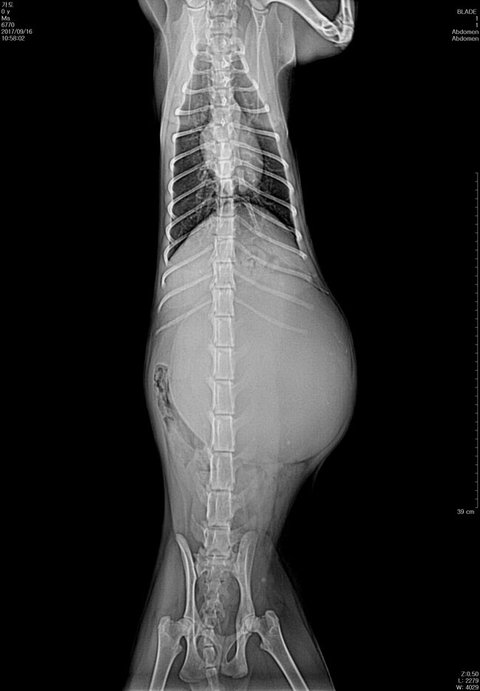

문제는 가토가 여자아이라 중성화하는데 위험할수도 있다고해서 엑스레이 찍었는데..

세상에 너무 깜짝놀랐어요.. 배가 2/3이 뭔가 혹?같은게 했어서요

(털에 가려있어서 잘 몰랐는데 찍고보니 무서웠어요 ㅜㅜ)

가토는 근육이 적당한편이래요 체중도 정상

혹같은게 몸통보다크죠..